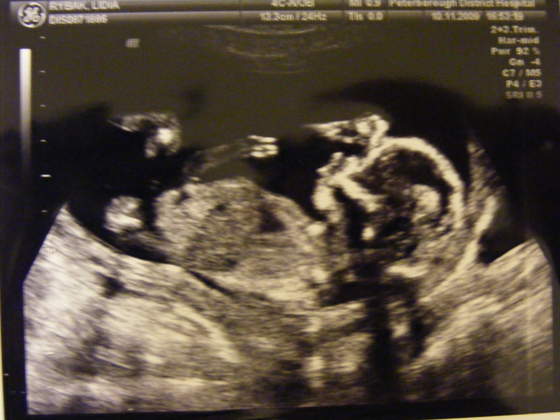

Oby szybko przeszło..

.

Tak ze jest ok:-)Teraz tylko czekam az sie wyprowadzimy od szwagierki;-)